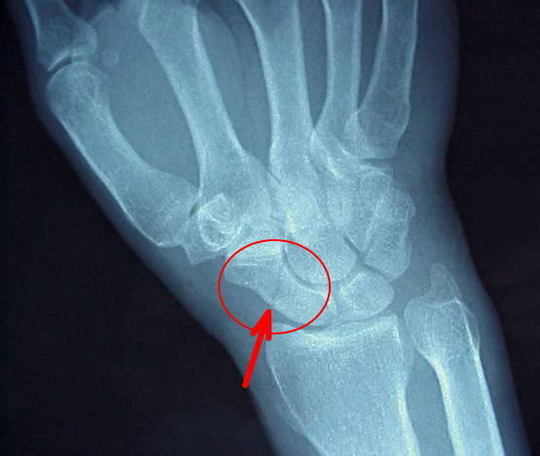

舟状骨骨折

そのため舟状骨の骨折は、通常のX線(レントゲン)写真の撮り方では骨折は見えにくく、見逃されてしまうこともあります。

手首の痛みが続き、動きにくくなれば、舟状骨骨折舟状骨偽関節も疑い、X線撮影が重要です。

しかし、初期には普通のX線写真でも発見されにくいことが多く、これが偽関節になる原因の1つです。

疑わしいものは、CTMRIをとると骨折があればはっきりします。